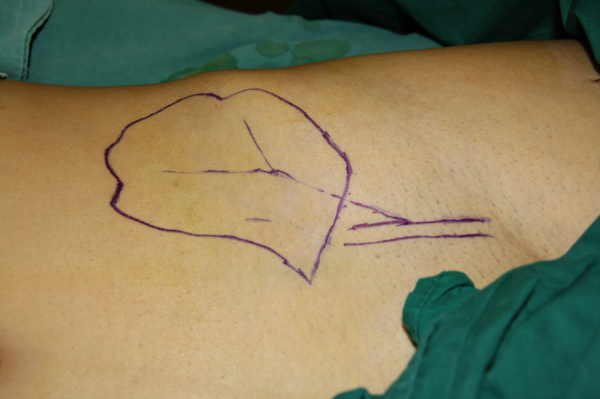

玉米机伤右足复合组织缺损,腓骨皮瓣修复,术后12天,伤口愈合良好,今日出院清创后

设计